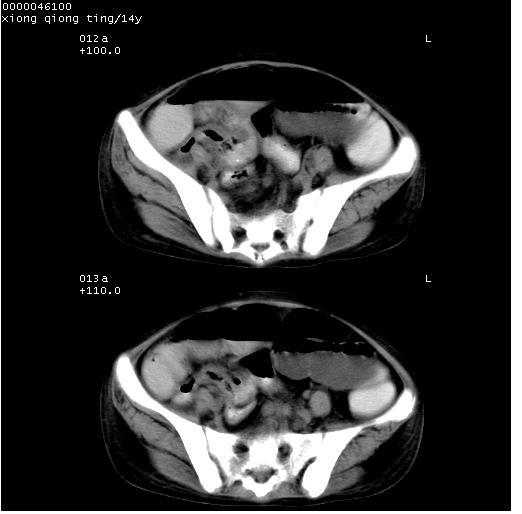

患儿 女,14岁。不规则发热一周,偶感头痛,无抽搐及呕吐。pe:神清,精神差,双侧瞳孔等大等圆,对光反射敏感,双肺未闻及明显啰音,心音有力,腹部触之似揉面感,下腹压痛,无反跳痛。

腹部b超提示:子宫缩小,盆腔积液,肝实质回声密集。

临床诊断:发热原因待查:1)腹部结核感染。2)伤寒?3)结缔组织病?

中下腹及盆腔ct轴位平扫+增强扫描(层厚10mm,螺距1.0,重建间隔10mm),图像如下:

(注:患儿检查当日上午9时口服胃肠道对比剂,下午3时许行ct扫描检查,未行对比剂直肠保留灌肠,检查当日患儿腹泻)

中下腹及盆腔ct轴位扫描(ps+ce)提示:腹部肠管明显充气扩张,并见数个不同宽度之气液平面;疑不全性肠梗阻或肠郁张。临床会诊考虑为患儿腹泻,肠郁张所致;后来未经特殊处理,患儿大便恢复正常,亦无腹胀。

临床出院诊断:1)结核性腹膜炎。2)腹膜后淋巴结结核。3)脂肪肝。